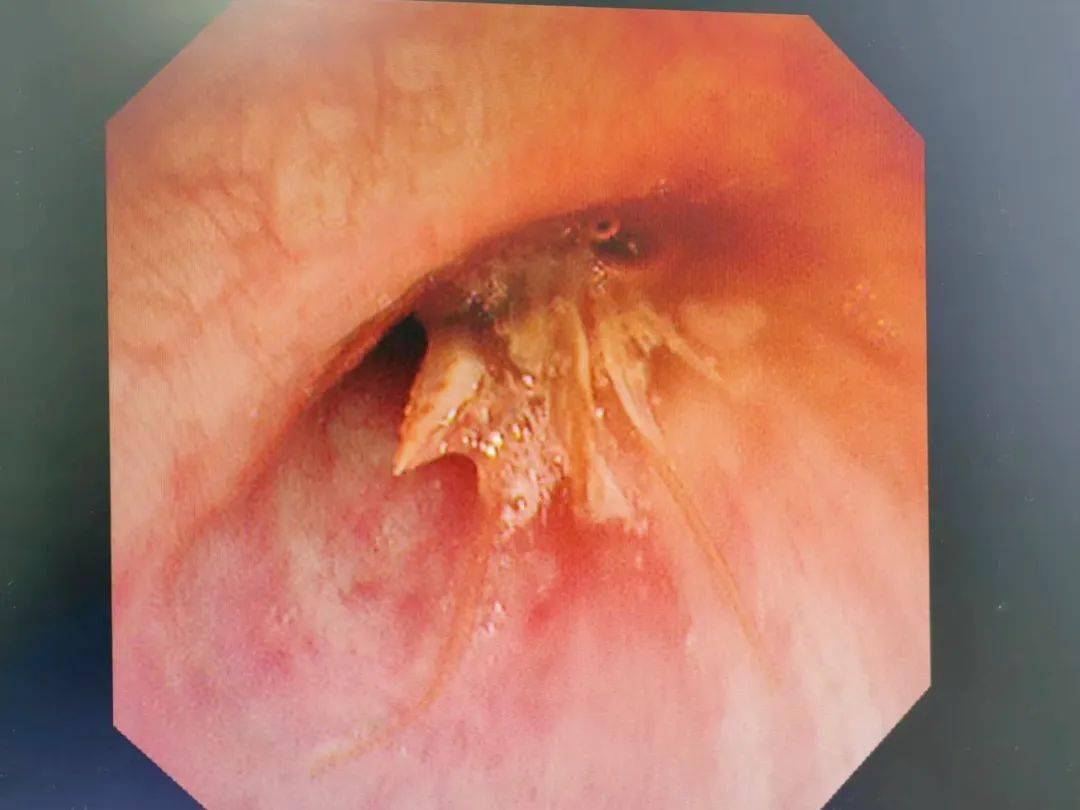

点评1,这是一例肺癌继发肺大泡,肺大泡破裂引起气胸的患者,由于患者